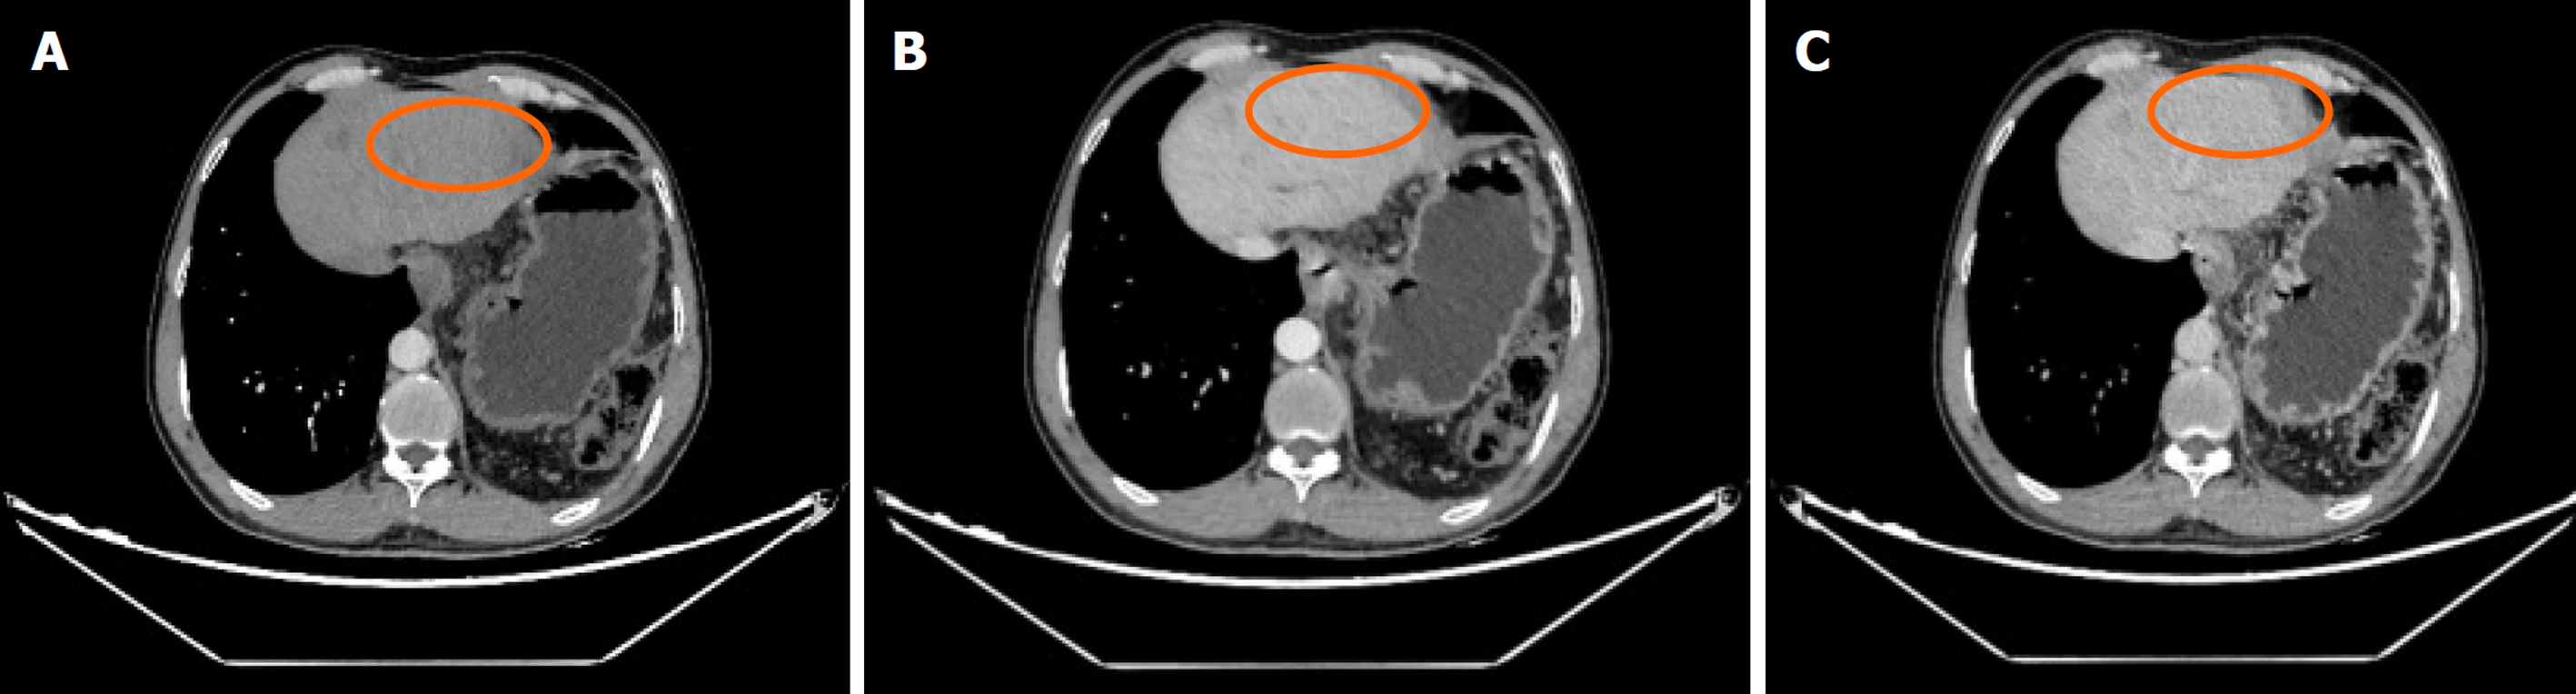

肝脏瞬时弹性测定: CAP 144 dB/m(<238), E 5.8 kPa(<7.3), 未见异常. 心脏超声: 左室假腱索, 二尖瓣+三尖瓣轻度反流. 胸部平扫计算机断层扫描(computerized tomography, CT): 双肺微小结节; 双肺条索灶; 左膈肌升高. 患者行上腹部增强CT示肝脏多发弱强化灶, 不除外肝癌(大者位于左内叶, 截面约1.3 cm×1.1 cm). 肝右叶门静脉期多发异常强化灶, 异常灌注可能. 肝硬化、门脉高压、食管胃底静脉曲张. 门静脉海绵样变. 肝多发囊肿. 胆囊术后; 脾术后. 肝内胆管扩张, 肝门区胆管壁增厚, 炎性病变?下腹部增强CT提示左肾多发结石; 左肾小囊肿; 腹膜后多发淋巴结. 盆腔增强CT提示直肠末端壁稍厚; 盆腔-直肠下段迂曲血管影(图1). 肝脏特异性对比剂增强磁共振(magnetic resonance, MR): 肝脏多发异常信号, 隔顶、左叶病变明显, 考虑肝癌可能. 肝硬化、门脉高压、食管胃底静脉曲张. 门静脉海绵样变. 肝多发囊肿. 胆囊术后、脾术后. 肝内胆管扩张, 肝门区胆管壁增厚, 炎性病变?(图2). 胃镜显示食管胃底静脉曲张(重度)及慢性非萎缩性胃窦炎, 肠镜显示直肠静脉曲张(重度)及结肠多发毛细血管扩张. 患者AFP正常, 影像学呈非典型多灶表现且合并显著门脉高压. 经多学科团队诊疗讨论, 为排除肝细胞癌并厘清基础肝病实体[门窦血管病变(porto-sinusoidal vascular disorder, PSVD)/结节性再生性增生(nodular regenerative hyperplasia, NRH)], 决定行影像引导下肝穿刺活检. 病理示肝板排列不规整, 肝窦灶性扩张, 局灶呈NRH样改变; 静脉束外围薄壁小血管疝入, 直接毗邻肝细胞板(图3). 免疫组化示CD10、CD34、CK19、CK8/18阳性; Masson染色显示汇管区及大血管周围胶原纤维增生, 弹力染色示血管壁弹力纤维增生, 网状纤维染色示局灶肝窦周网状纤维增生. 全基因组测序发现CFTR基因杂合错义变异c.374T>C(p.Ile125Thr).